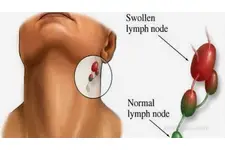

Bu belirtiler genellikle kişiden kişiye değişir ve yağ bezesinin boyutuna, konumuna ve bireyin vücut yapısına bağlı olarak farklılık gösterebilir. Tanı Yöntemleri Omuzda yağ bezesi tanısı genellikle fiziksel muayene ile konulmaktadır. Ancak, bazı durumlarda doktor, kütlenin yapısını daha iyi değerlendirmek için ek testler isteyebilir: